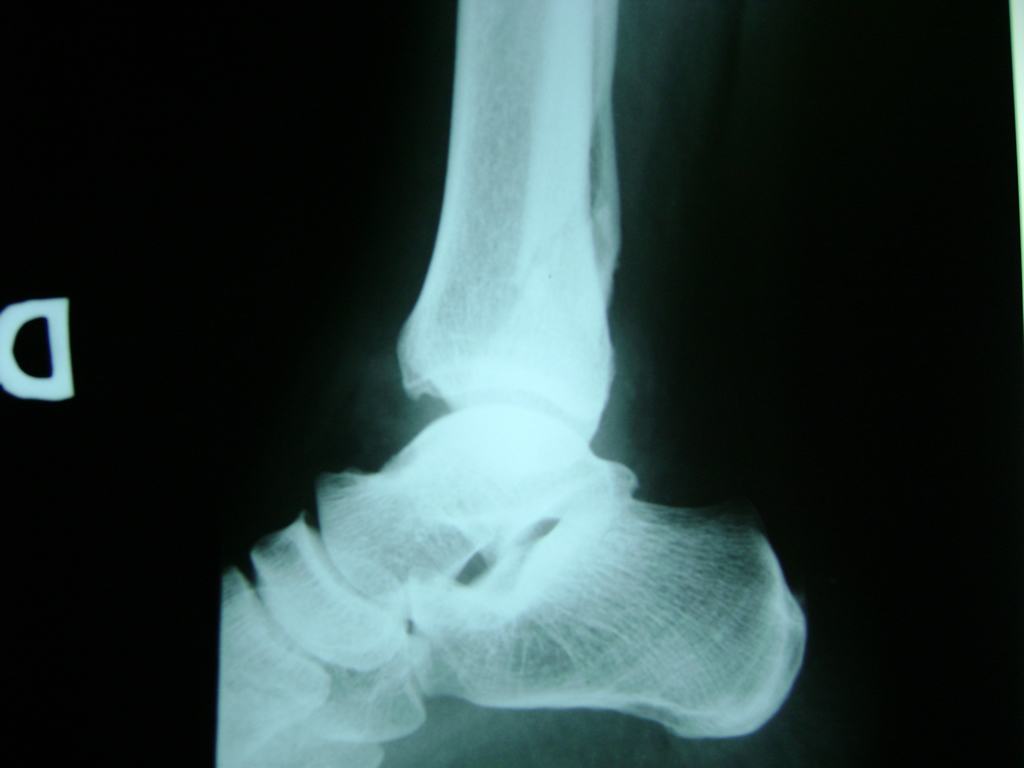

Una fractura de tobillo es la rotura de uno o más de los huesos del tobillo. Estas fracturas pueden ser:

- Parciales (el hueso está sólo parcialmente fisurado, no del todo).

- Completas (el hueso está perforado y está en 2 partes).

- Producirse en uno o ambos lados del tobillo.

Algunas fracturas de tobillo pueden requerir cirugía si:

- Los extremos de los huesos están desalineados entre sí (desplazados).

- La fractura se extiende hasta la articulación del tobillo (fractura intra-articular).